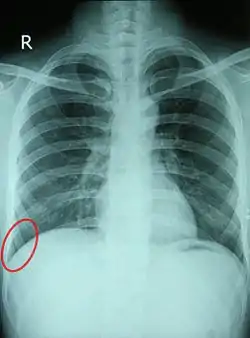

![]() Chest X-ray of a 30-year-old healthy man, with the costodiaphragmatic recess label in red ellipse | |

The costodiaphragmatic recess, also called the costophrenic recess or phrenicocostal sinus,[1] is the posterolateral fringe of the pleural space, a potential space around the lung inside the pleural cavity. It is located at the acutely angled junction ("reflection") between the costal and diaphragmatic parietal pleurae, and is interpreted two-dimensionally on plain X-rays as the costophrenic angle. It measures approximately 5 cm (2.0 in) vertically and extends from the eighth to the tenth rib along the mid-axillary line.

In anatomy, the costophrenic angles are the places where the diaphragm (-phrenic) meets the ribs (costo-).

Each costophrenic angle can normally be seen as on chest x-ray as a sharply-pointed, downward indentation (dark) between each hemi-diaphragm (white) and the adjacent chest wall (white). A small portion of each lung normally reaches into the costophrenic angle. The normal angle usually measures thirty degrees.